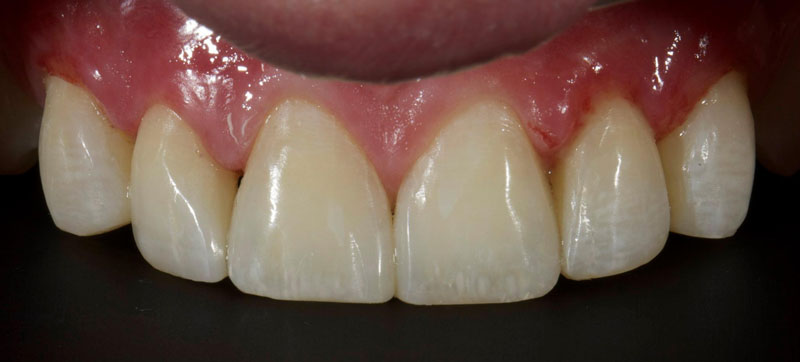

- Single Tooth: This is a microdontia localized to one tooth. Most peg laterals seen in a general dental practice setting will be of this type. See Fig. 3 (pre-op) and Fig. 4 (immediate post-op treated with direct resin).